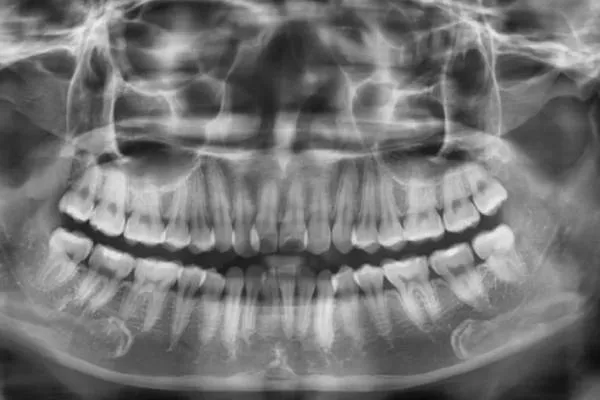

Dental X-rays (periapical or panoramic)

– First-line imaging for most tooth problems.